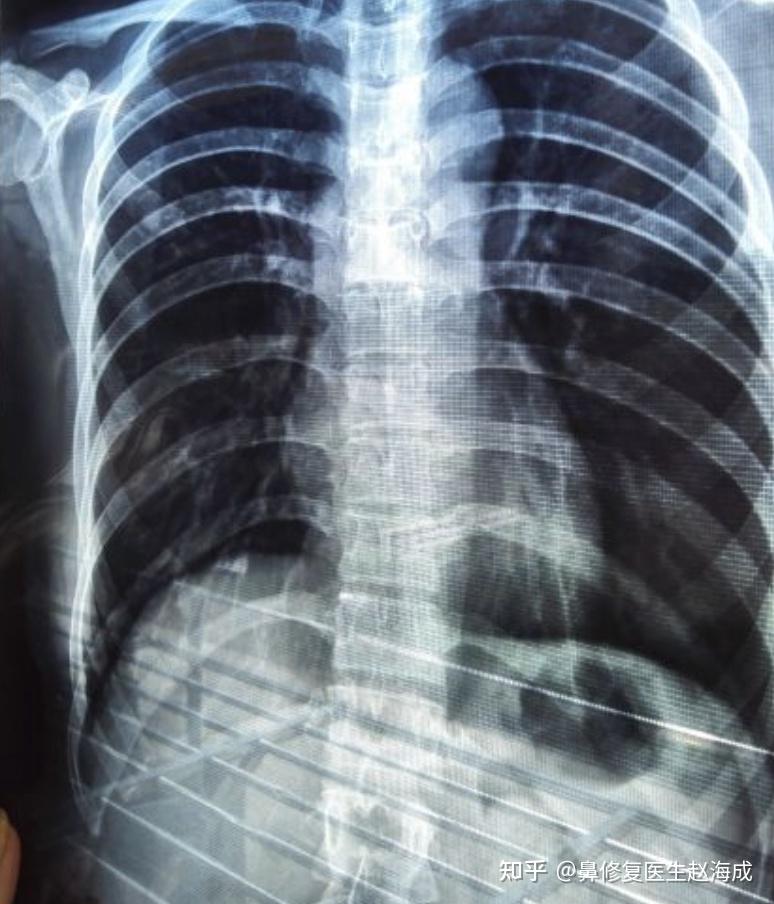

麻烦哪位专家给我看看胸部片,右侧肋骨上的白色地方是怎么回事,感觉就